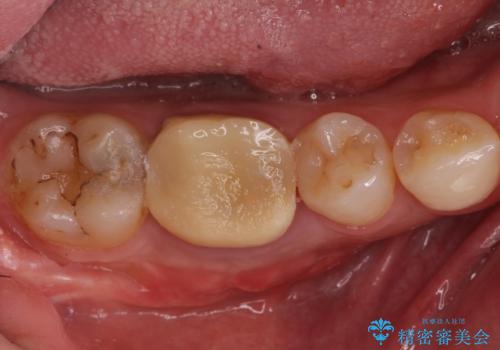

- 左上5 セラミックインレー/77,000円費用は治療当時の料金となります

適合の良いインレーは段差がない上にセラミックは汚れがつきにくい材料であるため今後の虫歯発生リスクを抑えることに繋がります。